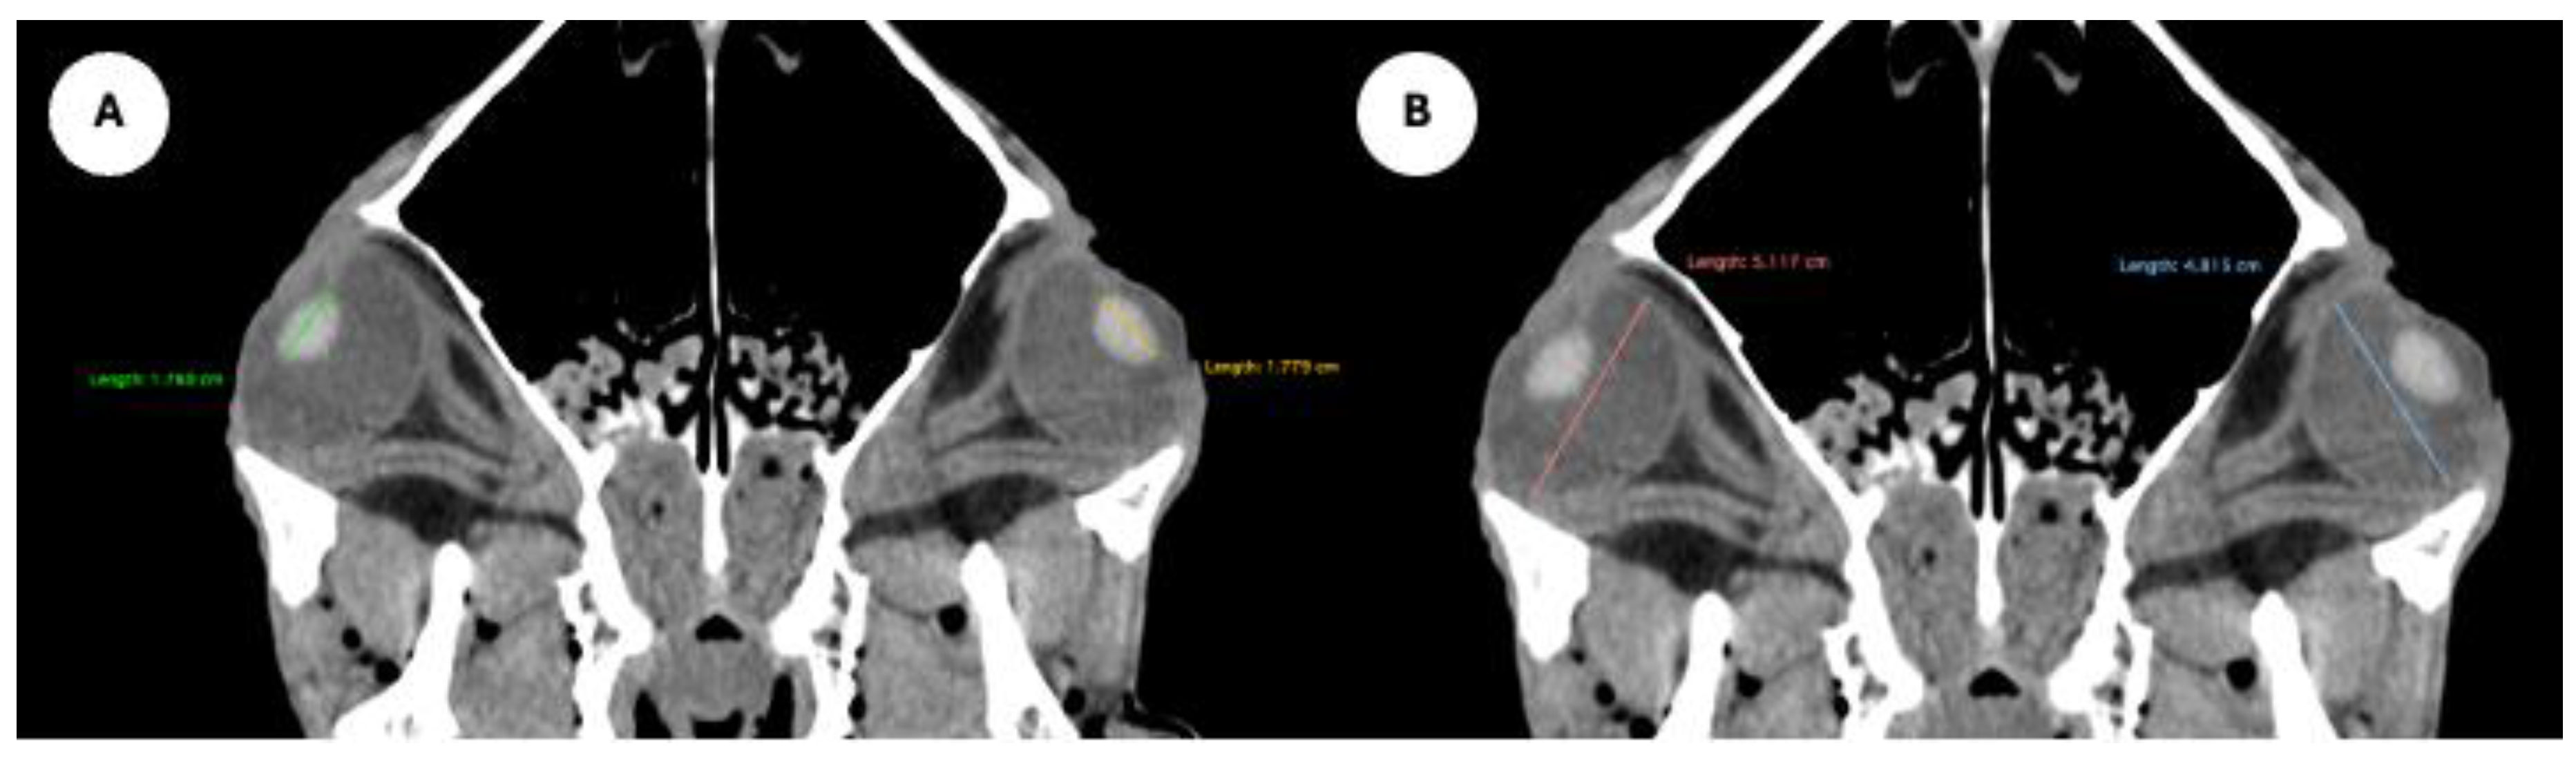

- Anterior chamber, posterior chamber, and lens densities: Attenuation values measured by placing regions of interest (ROIs) centrally in each structure (Figure 3).

- Anterior and posterior chambers width: Maximal lateromedial distance across the anterior and posterior chambers. (Figure 5)